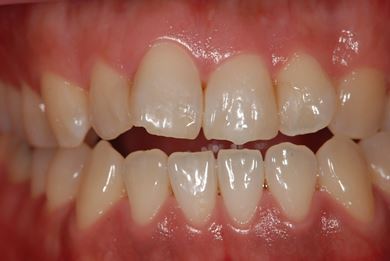

| 性別/年齢 | 男性 / 32歳 | ||||||||||||||||||||||||||||||||

| 主訴 | 銀歯がはずれたところの治療と、インプラント治療相談。 | ||||||||||||||||||||||||||||||||

| 治療方針 | 欠損部分をインプラント治療により、機能的・審美的回復を行う。 | ||||||||||||||||||||||||||||||||

| 治療内容 | インプラント2本、ハイブリッドセラミッククラウン2本 | ||||||||||||||||||||||||||||||||

| 総治療費 | 399,000円 | ||||||||||||||||||||||||||||||||

| 治療期間 | 7ヶ月 |